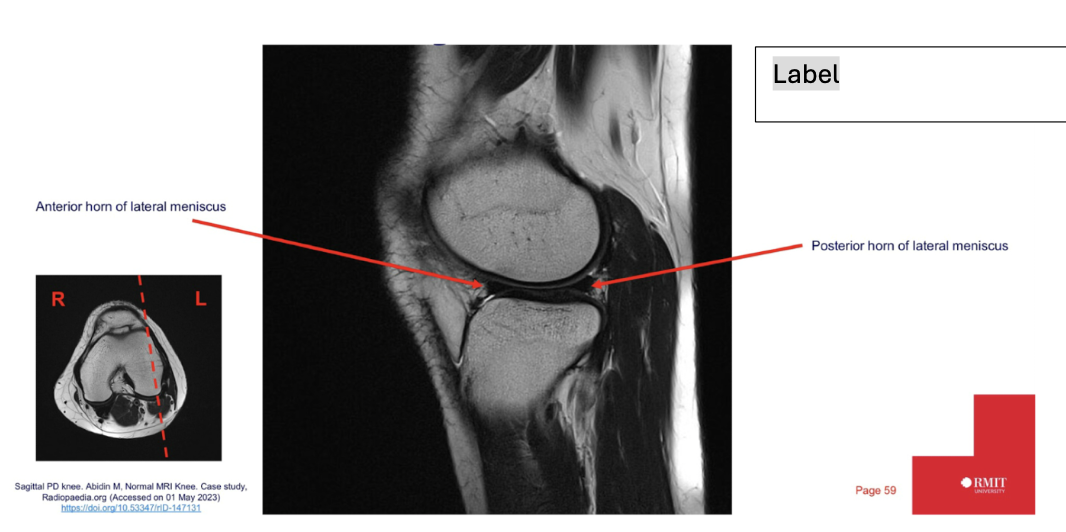

What is the sequence and why?

• T1 – fluid is dark but fat is bright

59

New cards

Label